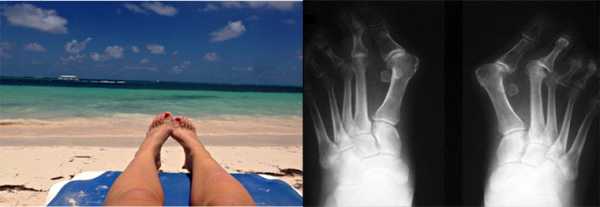

Hallux Valgus - вальгусная деформация (косточка на большом пальце ноги)

Косточка на большом пальце ноги, вальгусная деформация первого пальца стопы, вальгусная деформация большого пальца стопы, халлюкс вальгус, Hallux Valgus, - все эти названия относятся к одной и той же патологии.

Hallux Valgus (Халлюкс Вальгус) - медиальная(внутренняя) девиация первой плюсневой кости и латеральная(наружная) девиация и внутренняя ротация (вращение вокруг своей оси) первого пальца стопы. По сути, является не простой деформацией первого плюсне-фалангового сустава, а сложной деформацией всего медиального луча стопы. Часто сопровождается симптомными деформациями второго пальца стопы. Выделяют две формы: халлюкс вальгус у взрослых и подростковый\ювенильный халлюкс вальгус.

Рентгенологическое определение углов при вальгусной деформации первого пальца стопы.